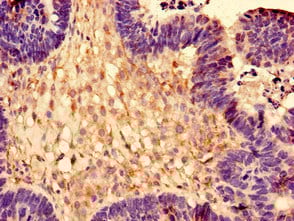

IHC (Immunohistochemistry)

(Immunohistochemistry of paraffin-embedded human ovarian cancer using AAA118129 at dilution of 1:100)